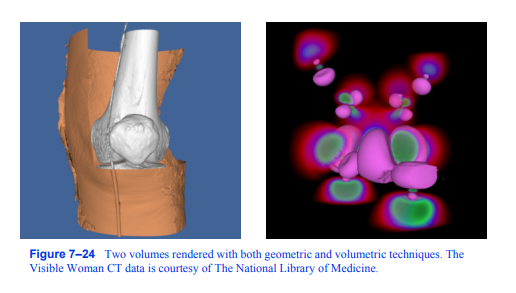

图7-24用几何和体积技术绘制的两个体块。的

可见女性CT数据由国家医学图书馆提供。

7.10混合体积和几何

虽然在体可视化中,体积通常是图像的焦点,但在场景中添加几何对象通常是有帮助的。例如,显示数据集的包围框或切割平面的位置和方向可以提高查看者对体积数据的理解。此外,在同一图像中同时使用几何和体积方法可视化体积数据也很有用。图7 - 24中的左图显示了人类膝盖的CT扫描,其中使用轮廓法提取皮肤等值面。使用标准图形硬件将此等值面渲染为三角形。皮肤的右上部分被切割以显示下面的骨头,这是使用软件射线投射技术和合成射线功能渲染的。在右侧图像中,使用几何等值面和体绘制技术可视化了铁蛋白的波函数值。

当使用图形硬件执行体渲染时,就像纹理映射方法一样,在场景中混合不透明的几何图形是微不足道的。所有不透明的几何图形都是图7-24用几何和体积技术渲染的两个体。可见女性CT数据由国家医学图书馆提供。242张高级计算机图形先渲染,然后半透明的纹理映射多边形以前后顺序混合到图像中。如果我们希望在场景中包含半透明的几何体,那么这个几何体和纹理映射的多边形必须在渲染之前进行排序。类似于纯几何场景,这可能涉及分割多边形以获得排序顺序。

如果使用软件体绘制方法,例如对象顺序飞溅方法或图像顺序射线投射方法,则可以通过渲染几何图形,捕获存储在硬件深度缓冲区中的结果,然后在体绘制阶段使用这些结果来将不透明几何图形合并到图像中。对于射线投射,我们将简单地将像素的深度值转换为沿视图射线的距离,并使用它来绑定我们在体绘制期间考虑的射线段。在体绘制期间为像素计算的最终颜色然后与使用over运算符的几何绘制产生的颜色混合。在对象顺序方法中,我们必须考虑每个样本的深度,并将其与该样本图像范围内每个像素处的深度缓冲区中存储的值进行比较。只有当样本位于该像素的几何图形前面时,我们才在每个像素处累积该样本对体积渲染图像的贡献。最后,将体渲染图像混合在几何图像上。